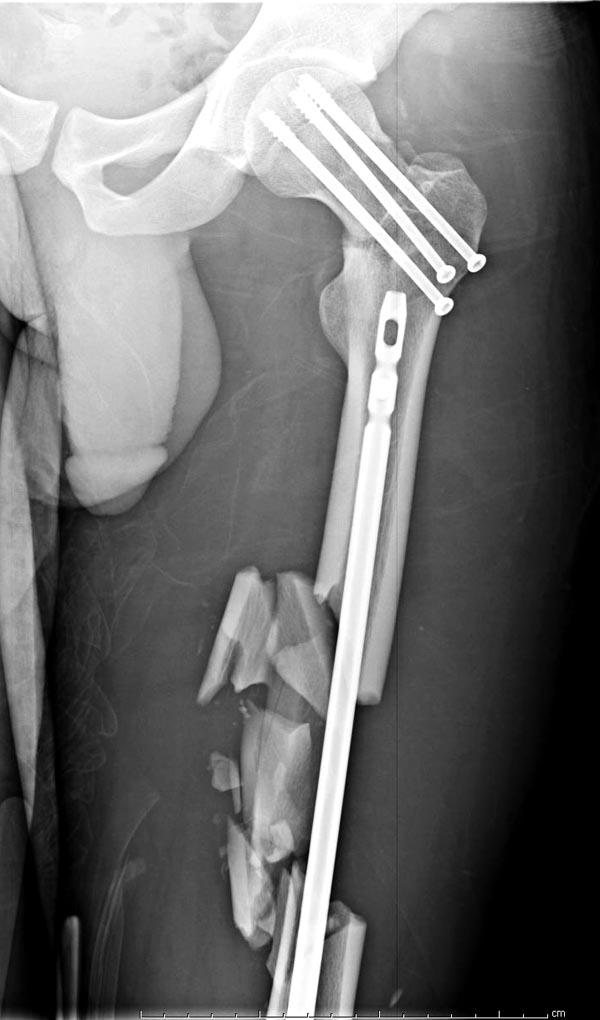

Здесь выставлен ренгенограммы больного, ему 21, травму получил в

результате высокоскоростной погони на украденной машине, которая

закончилась смертью трех остальных“боевых комрадов”. Начатую коллегой

открытую операцию на шейке пришлось закончить мне, установкой винтов и

ретроградной фиксацией бедра. Выписка в обычное сроки и наблюдался

амбулаторно. Каждый раз напоминали о возможности осложнений ввиде

несращения! По истечению 4 месяцев появились признаки варусной

деформации. На СТ срезах несращение шейки и бедра. Риминг, замена на

более толстый гвоздь и вальгусная остеотомия.